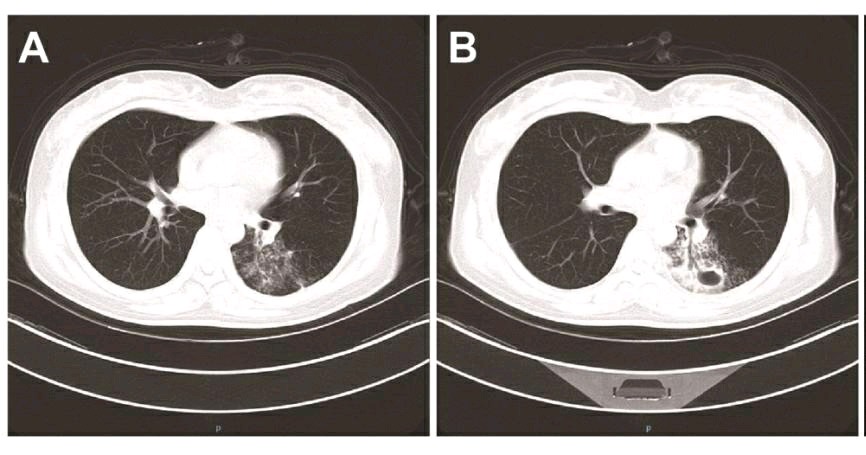

小宁胸部CT检查提示:左下肺实变并空洞,考虑感染或吸入性肺炎。结合血沉升高,小宁考虑是肺结核,排除新冠肺炎。

鉴别第二点是根据她的CT表现,是空洞型肺结核典型表现,特点是空洞内壁光滑,周围有很多形态的卫星灶,表现为粟粒状小斑点,还有一些小树芽和小斑片影,就像地球周围环绕了很多卫星。

因为肺结核杆菌含有大量脂肪成分,这些脂肪液化后,可以与周围的钙离子发生皂化反应,形成脂肪酸盐,像肥皂颗粒一样具有清洁功能,加上结核杆菌的破坏比较彻底,所以肺结核的空洞常常比较光滑,像被肥皂水洗过